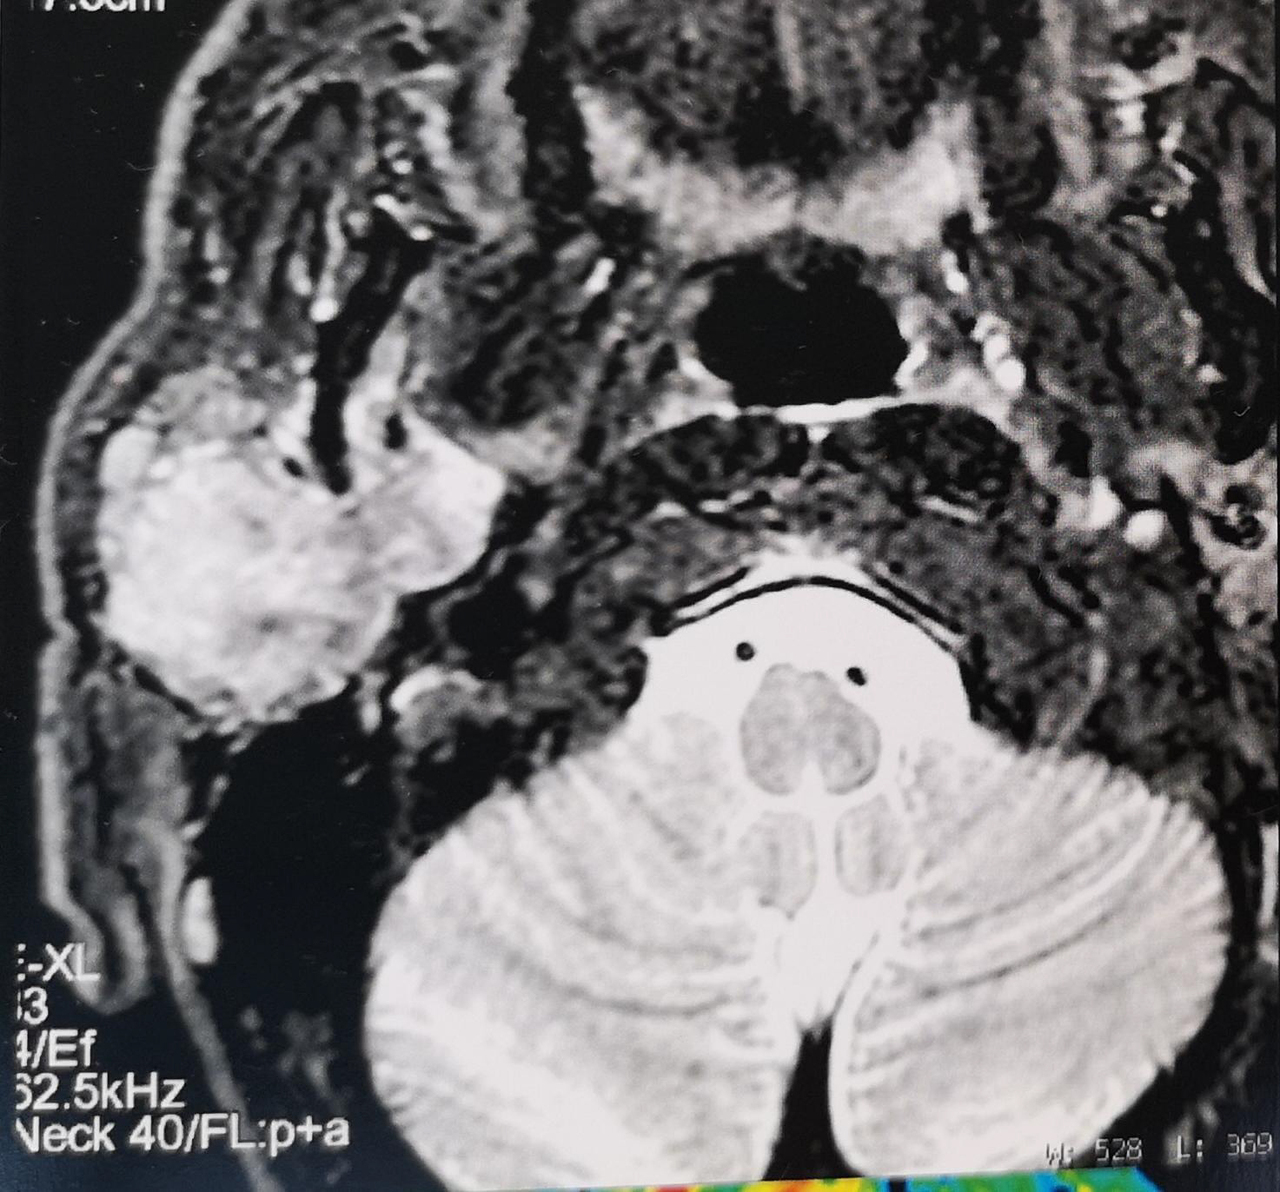

Elle a remarqué, depuis quelques mois, une « boule » en avant de l’oreille à droite, en regard du lobule. Elle n’a pas mal mais est un peu inquiète.

À rechercher devant toute pathologie de la région parotidienne. Un testing musculaire doit être réalisé. Sa présence oriente vers la malignité.

En cas de tumeur maligne, il peut exister des ganglions cervicaux.